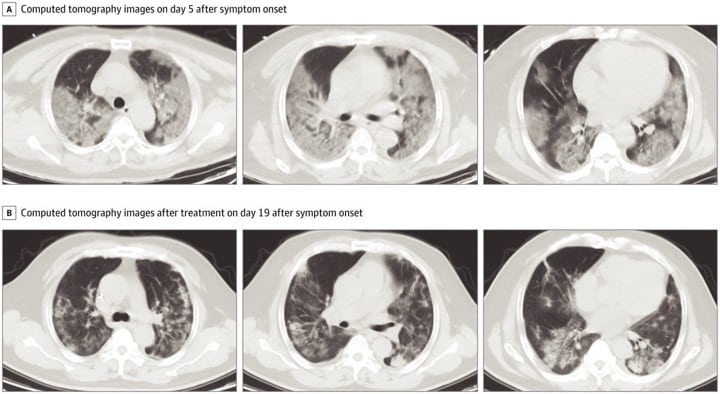

اسکن بیماران کرونا لکههای سفید رنگی دارد که رادیولوژیستها از آن به عنوان «کدورت شیشه مات» یاد میکنند.این علامت نشانگر عفونت شدید COVID-19 و ناشی از تجمع مایع در ریهها است. اما این علامت به تنهایی برای شناسایی ویروس کرونا مفید نیست. «این علامت در سایر عفونتها نیز قابل مشاهده است. عفونتهای باکتریایی، ویروسی یا حتی گاهی غیر عفونی و حتی در استعمال سیگار الکترونیک.»اما در مورد علائم ریه کرونا گرفته، لکه های قابل توجهی در سی تی اسکن ریه کرونایی هستند که تا لبههای ریههای بیمار امتداد مییابند. این چیزی نیست که خیلی شایع باشد. ما این مورد را در سندرم تنفسی حاد (SARS) و سندرم تنفسی خاورمیانه (MERS) مشاهده کردهایم.SARS و MERS هر دو از خانواده کرونا ویروس هستند.ریه و کرونا با هم مرتبط هستند و برای تست سلامتی ریه باید مطمئن شوید که دچار کرونا نشدهاید و یا اگر مبتلا شدید، کرونا را به سرعت مداوا کنید. شما از طریق درمانکده میتوانید تست کرونا در خانه یا محل خود بدهید و جواب را در ۲ روز کاری دریافت کنید:تجزیه و تحلیل نزدیک به ۱۴۰ اسکن ویروس کرونا نشان میدهد که «کدورت شیشه مات» در هر دو ریه از مشخصههای سی تی اسکن ریه کرونایی است.A: سی تی اسکن در روز پنجم ظهور علائمB: سی تی اسکن در روز نوزدهم ظهور علائم

محققان بیمارستان Zhongnan دانشگاه ووهان اسکن بیماران را تجزیه و تحلیل کردند. اکثر آنها مردان مسنی بودند که مشکلات زمینه ای داشتند. تصاویر بالا سی تی اسکن ریه کرونایی یک بیمار ۵۲ ساله است.اولین گروه اسکنها (گروه A) در ۷ ژانویه، پنج روز پس از شروع علائم در بیمار، انجام شد. «کدورت شیشه مات» در پایین هر دو ریه قابل مشاهده است.این مرد از ۷ تا ۱۲ ژانویه تحت درمان قرار گرفت. پس از آن، به نظر میرسید وضعیت او بهتر شده است. سری دوم اسکنها (گروه B)، که در ۲۱ ژانویه انجام شد، نشان می دهد که بسیاری از لکه های سفید کوچک یا ناپدید شده اند.وضعیت بسیاری از بیماران ویروس کرونا به سرعت وخیم و «کدورت شیشه مات» آنها پس از چند روز بارزتر میشود.وضعیت بسیاری از بیماران ویروس کرونا به سرعت وخیم و «کدورت شیشه مات» آنها پس از چند روز بارزتر میشود.وضعیت بسیاری از بیماران ویروس کرونا به سرعت وخیم و «کدورت شیشه مات» آنها پس از چند روز بارزتر میشود.